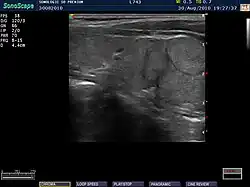

Ultrasound imaging of the thyroid gland (right lobe longitudinal) in a person with Hashimoto thyroiditis

Ultrasound imaging of the thyroid showing Hashimoto's thyroiditis

An ultrasound may be useful in detecting Hashimoto thyroiditis, especially in those with seronegative thyroiditis,[13] or when patients have normal laboratory values but symptoms of autoimmune thyroiditis.[47] Key features detected in the ultrasound of a person with Hashimoto's thyroiditis include "echogenicity, heterogeneity, hypervascularity, and presence of small cysts."[13] Images obtained with ultrasound can evaluate the size of the thyroid, reveal the presence of nodules, or provide clues to the diagnosis of other thyroid conditions.[47]